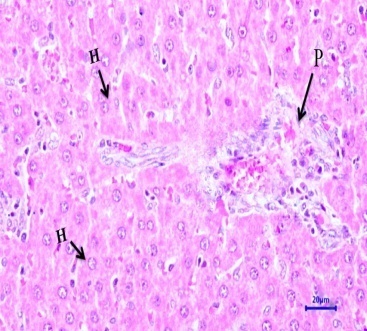

Fig. 12: Histopathological examination of experimental rat liver after 21 d treatment (HandE, 400 X magnifications). Liver section of (I) Normal control, (II)Diabetic control,(III)EOAM (EOFAE 250+AMLEAE250 mg/kg bw),(IV) EOAM (EOFAE 500+AMLEAE 250 mg/kg bw, Combination of (V)EOAM (EOFAE 500+AMLEAE250+Glib 5 mg/kg bw),(VI)EOAM (EOFAE 500+AMLEAE 250+Glib 5 mg/kg bw),(VII)Glibenclamide5 mg/kg bw.[Hepatocyte (HC), Normal Portal Triad (P), Hepatocellular Vacuolation (V), Portal Triad (P) and Hepatocyte (H)]

Histopathological studies

Histopathological examination of the experimental rat liver after 21 d treatment indicates that the liver section of normal control rats (NC) did not revealed any lesion of pathological significance as shown in fig. 12 (I). Liver section of diabetic control rat showed multifocal moderate hepatocellular vacuolation (microvesicular) as shown in fig. 12 (II). Liver section of diabetes-induced rats treated with low dose and high dose did not revealed any lesion of pathological significance as shown in fig. 12 (III) and (IV). Combination of low dose and high dose with glibenclamide also did not revealed any lesion of pathological significance as shown in fig. 12 (V) and (VI). Standard drug did not revealed any lesion of pathological significance as shown in fig. 12 (VII). Histopathology of the liver of STZ induced diabetic animals showed that there were hepatic changes, mild portal inflammation and hepatocellular vacuolation. After treatment of the animals by EOAM and glibenclamide, there was normal histology and reduced severity of the histopathological changes caused by STZ. The present study shows that the EOAM treated group III have significant antioxidant and antidiabetic activity as compare to diabetic control STZ induced animals. Equiproportion combination of both extracts shows significantly decreased in oxidative stress as evidenced by improved activities of antioxidant enzymes like superoxide dismutase, reduced glutathione. From the histological studies the liver section of group V and VI may have some interactions and liver section of diabetes-induced rats groups III, IV treated with EOAM and VII treated with well known sulfonylurea drugs like glibenclamide did not revealed any lesion of pathological significance, where the group III shows good significant effect (p<0.001) as compare to STZ-induced diabetic rats.